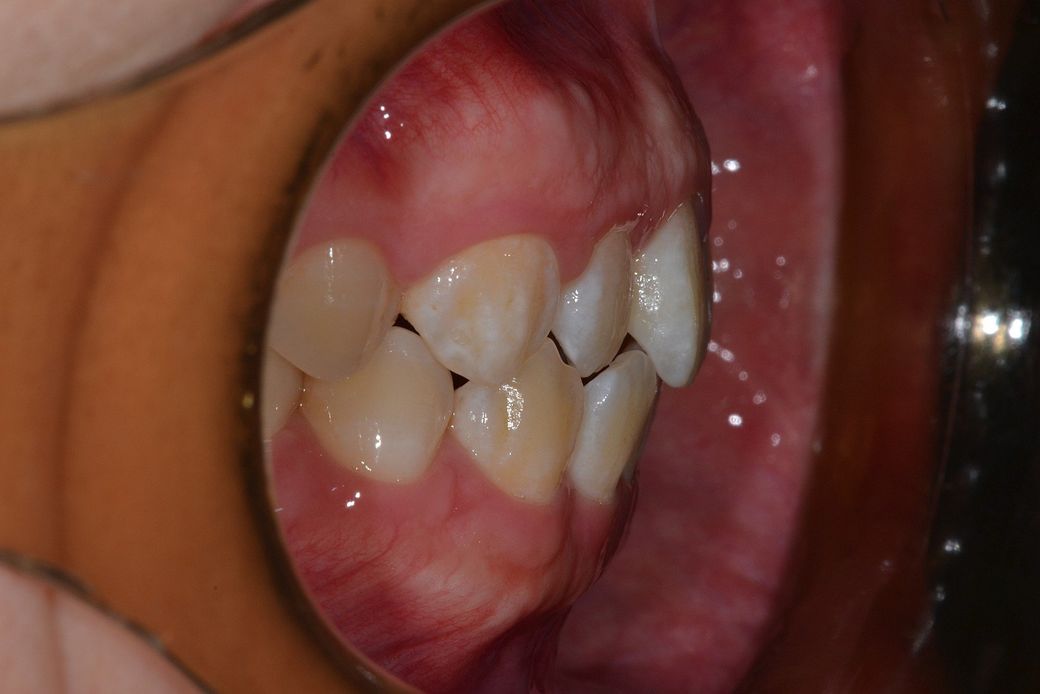

치과에서 사진찍었는데 사진을 보니 잇몸이 돌출된 느낌이 들어서요 치아 각도는 정상같아 보이는데 잇몸이 전체적으로 앞으로 쏠린느낌이 듭니다

잇몸도 다른분들은 붉은색이나 선홍색을 띄는데 저는 치아 뼈 때문인지 하얀색도 많고 울퉁불퉁 한 느낌이에요

• 2번 째 사진